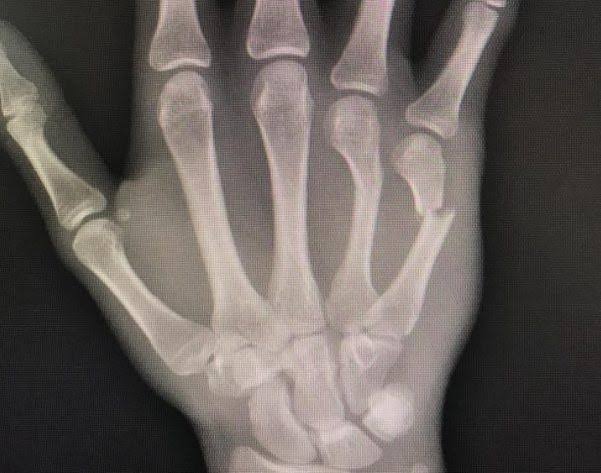

拳を握った状態で強打することによって起こる中手骨頚部の骨折を“ボクサー骨折”といいます。中手骨は解剖学的に頭部・頚部・骨幹部・基部に分かれ、骨折は頚部が1番多いといわれています。

中手骨頚部骨折は第2〜5指のいずれにも発生しますが、第4・5中手骨の発生頻度が高いといわれており、多くはパンチ動作で発生するためボクサー骨折とも呼ばれますが、ボクシングや空手などスポーツによって引き起こされることはまれです。

骨折部は手のひら側に曲がる変形(屈曲変形)が発生するため、骨折した指の拳がへこんで見えるのも特徴です。